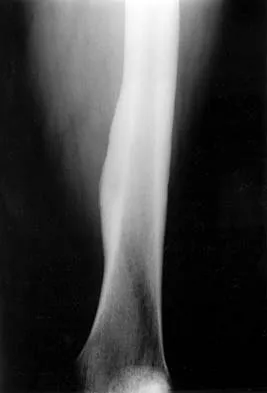

What is the most appropriate next step in the work-up of a patient with the asymptomatic lesion shown in Figure 23?

Detailed Explanation

The eccentric metaphyseal location, skeletal maturity, narrow zone of transition, and lack of symptoms suggest a benign process and are consistent with a healed nonossifying fibroma. These lesions typically fill in (ossify) with skeletal maturity, eventually remodeling and disappearing. Radiographic monitoring is indicated. Biopsy is not recommended unless the lesion changes radiographically. Marks KE, Bauer TW: Fibrous tumors of bone. Orthop Clin North Am 1989;20:377-393. Bullough PG, Walley J: Fibrous cortical defect and non-ossifying fibroma. Postgrad Med J 1965;41:672-676.